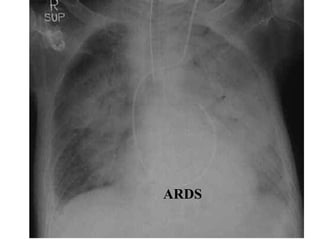

ARDS

• difficult to distinguish from cardiogenic

pulmonary oedema or pneumonia.

• usually causes more uniform opacification.

• Pleural effusions are not typical.

• Kerley B lines are uncommon

• Air bronchograms found in both.

• The distinction from pneumonia is on the

basis of non-radiological investigations.